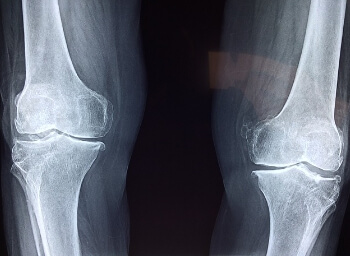

1. 부상

무릎 주변의 인대와 근육이 과도한 활동으로 인해 자신도 모르게 늘어나거나 찢어지면 통증이 발생하기도 합니다.

또한, 무릎 관절을 완충시키는 고무와 같은 연골인 반월판이라는 것이 갑작스러운 움직임으로 인해서 비틀림이 생기면 찢어지는 손상이 생길 수 있어서 통증이 발생하기도 합니다.

3. 구조적 문제

원천적으로 슬개골의 잘못된 정렬로 인해서 관절 전체에 고르지 않은 압력이 가해지면 결과적으로 통증이 유발되기도 하기도 하며, 연골이나 뼈의 작은 조각이 부러져 관절에 유동적으로 떠다니면서 무릎에 통증과 고통이 유발됩니다.

4. 비만

비만은 여러가지 건강과 관련한 문제를 유발하는데, 무릎 관절의 건강도 예외는 아니어서 정상범위를 넘어선 과도한 체중은 무릎의 관절에 부담을 주어서 염증을 유발하게 되고 결과적으로 관절의 통증을 유발합니다.

5. 근력의 부족

전반적으로 신체의 근육량이 감소하게 되면 근골격계에도 영향을 미치게 되는데요. 무릎 주변의 근육이 약화되면 관절에 적절한 지지력을 제공하기 못하기 때문에 관절에 스트레스가 증가하여 결과적으로 통증이 유발되기도 합니다.